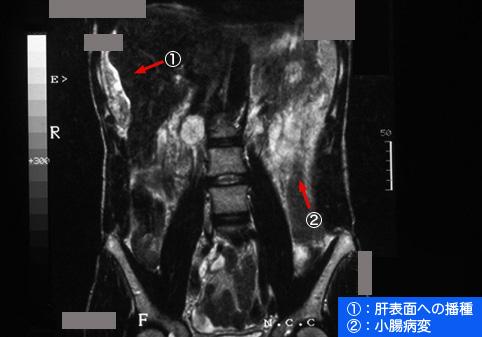

A case of Peutz-Jeghers syndrome which was associated with advanced mucinous adenocarcinoma in the small intestine.

Tumor-like lesions/Peutz-Jeghers syndrome

MRI